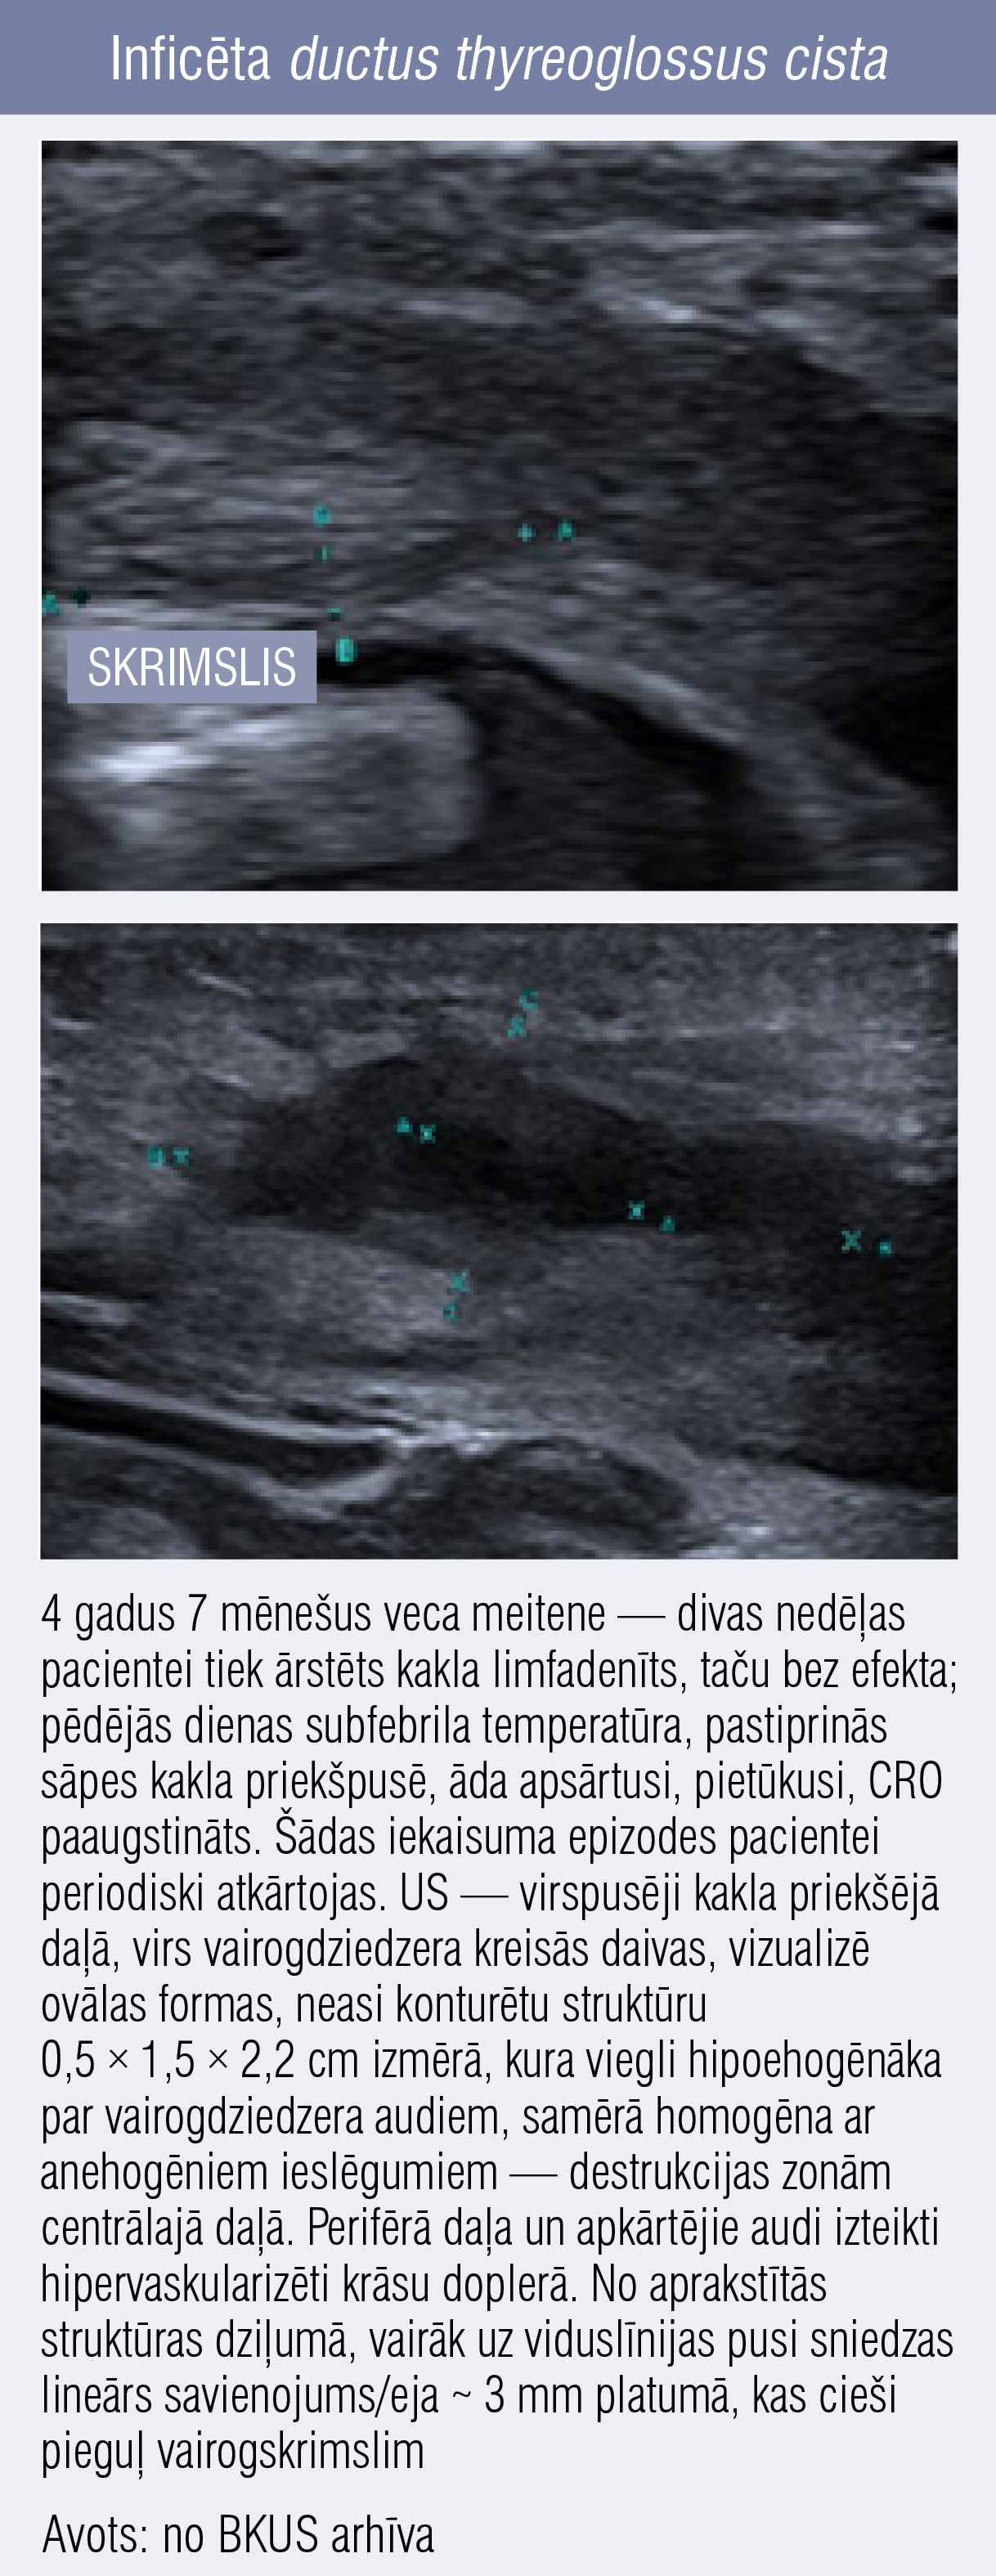

Inficēta ductus thyreoglossus cista Inficēta ductus thyreoglossus cista

7. attēls

Inficēta ductus thyreoglossus cista

Gadījumos, kad US vizuālā atrade atgādina limfmezgla cistisku destrukciju, svarīgi pievērst uzmanību atrašanās vietai kaklā — izmaiņas vērojamas viduslīnijā vai sānos. Limfmezgli parasti ir laterāli izvietoti un daudzfokāli.

Ja konstatē fokālas cistiskas izmaiņas kakla viduslīnijā, tad diferenciāldiagnozē jāiekļauj iedzimtas tireoglosālā kanāla cistas iekaisīgas izmaiņas vai arī dermoīdas cistas (7. attēls).